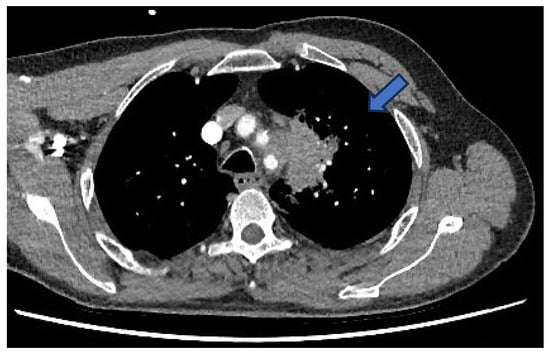

During further investigation, contrast-enhanced CT of the thorax, abdomen, and pelvis revealed a 5.5 cm mass in the upper lobe of the left lung (Figure 2). Notably, this mass appeared to invade through tissue planes, encroaching into the mediastinum and involving the arch and proximal descending aorta. There were no other lung findings or suspicious bony lesions.

Figure 2. CT—left-sided lung mass (blue arrow) invading into the mediastinum, involving the aortic arch and proximal descending aorta.